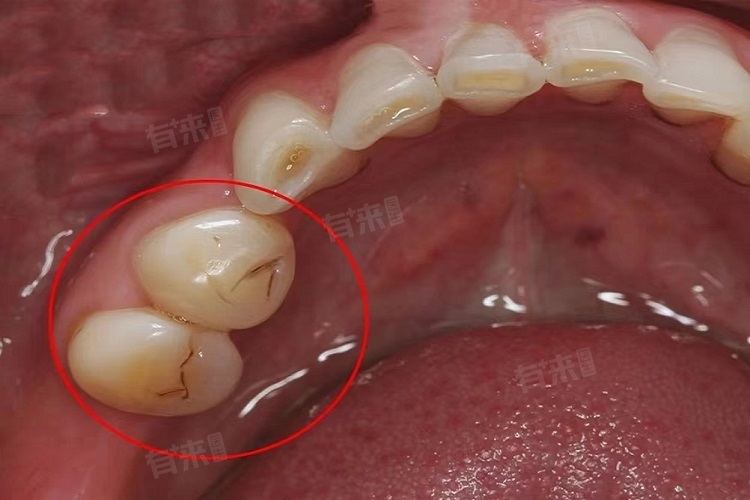

3、龋齿:口腔内的细菌会分解食物中的糖分,产生酸性物质,这些酸性物质会持续侵蚀牙齿,致使牙齿表面的牙釉质脱矿,进而形成龋洞。龋洞在外观上常常呈现为黑缝状。在龋齿的早期阶段,医生通常会采用补牙的方式进行治疗,即使用专业工具去除龋坏组织,然后用合适的补牙材料进行填充,恢复牙齿的外形和功能。

此外,在日常生活中,由于咀嚼过硬的食物,如核桃、骨头等,或者遭受外力撞击,都有可能导致牙齿出现隐裂。隐裂初期可能不易察觉,但随着时间的推移,裂缝会逐渐加深,并且容易积聚食物残渣和色素,从而使牙齿表面呈现出黑缝。对于浅表的牙齿隐裂,可以通过调整咬合关系,减轻患牙的受力负担。若隐裂较深,已经累及牙髓,则需要先进行根管治疗。